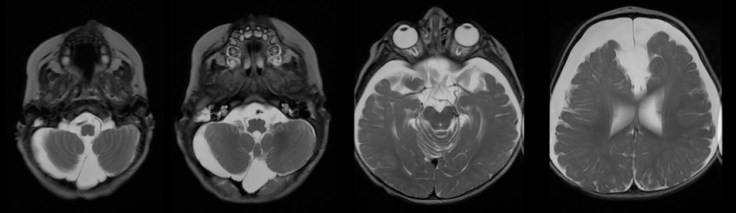

l’IRM identifie les veines et distingue l’épanchement sous-arachnoïdien du sous-dural qui lui est parfois associé. elle permet aussi de distinguer les macrocranies essentielles vraies des autres causes de macrocrânie : macrocéphalie vraie (syndrome de Sotos)

ici, macrocrânie révélatrice d’un déficit de l’oxydation des acides gras à chaînes courtes (SCAD)